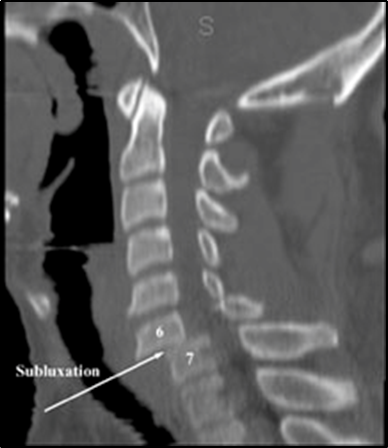

8. Subaxial injury classification & severity score system (SLIC system)

1) Morphology : no abnl (0), compression (1), burst (2), distraction (3), rotation/translation (4)

2) Neurologic status: intact (0), root injury (1), complete cord injury (2), incomplete cord injury (3), continuous cord compression in the setting of neuro deficit (4)

3) Disco-ligamentous complex : intact (0), indeterminate (1), disrupted (2)

-> 4미만 (non op), 4점 (op 또는 non op), 5점 이상 (op!)